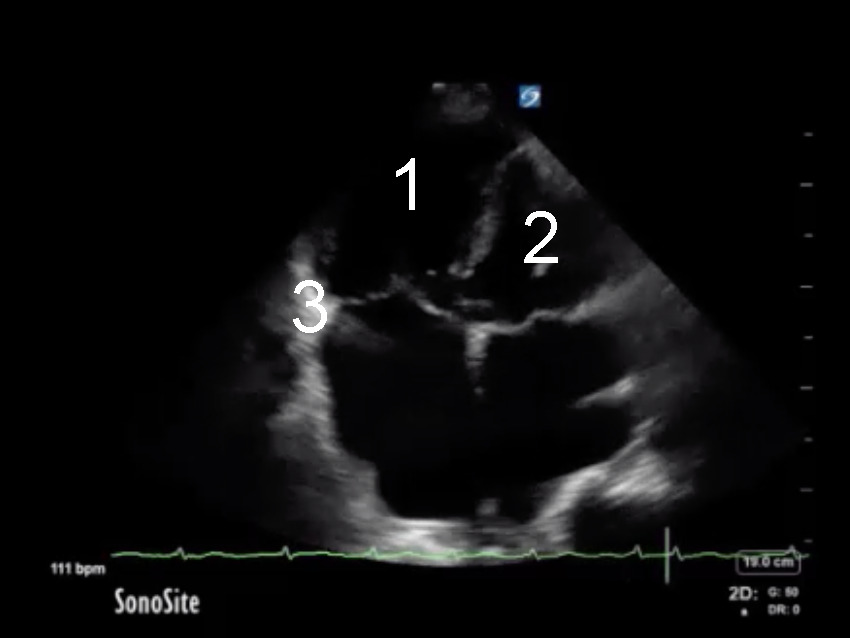

Cardiac 2 RV Assessment Depressed Image

Right Ventricle (RV)

Left Ventricle (LV)

Tricuspid Annulus